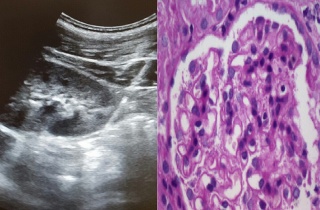

´çÀÏ ½ÅÀåÁ¶Á÷°Ë»ç »õ ¿ª»ç '¹Ì·¡¾ÆÀ̾ØÁö Á¶º´¼öÀÇ¿ø'

¹Ì·¡¾ÆÀ̾ØÁö Á¶º´¼öÀÇ¿øÀÌ °³¿ø 3³â¿© ¸¸¿¡ ´çÀÏ ½ÅÀåÁ¶Á÷°Ë»ç(½Å»ý°Ë) 250·Ê¸¦ ´Þ¼ºÇÏ¸ç ±¹³» ÃÖÃÊ ½ÅÀ庴Àü¹®Å¬¸®´ÐÀ¸·Î¼­ÀÇ 2016-08-01 16:10:50